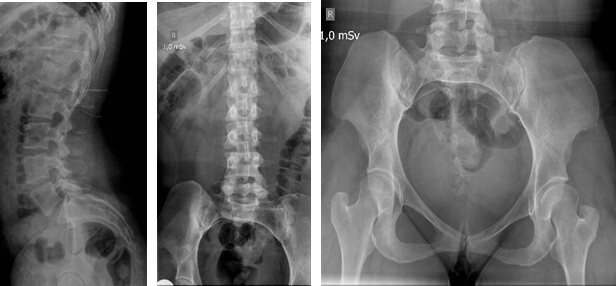

La condrodisplasia de Grebe es un trastorno raro autosómico recesivo que pertenece al grupo de las osteocondrodisplasias. Clínicamente se caracteriza por un severo dismorfismo con una marcada micromelia y deformidad de las extremidades inferiores y superiores. Conocer este tipo de síndrome orienta a dar mejores diagnósticos y permite el diagnóstico diferencial con patologías más comunes, como la acondroplasia. Se presenta una paciente de 35 años con diagnóstico de síndrome de Grebe desde los 10 años. El síndrome de Grebe tiene una muy baja incidencia; por este motivo, es poco conocido por el cuerpo médico en general y aun menos para los ortopedistas, quienes serán los encargados de tratar a estos pacientes. AbstractGrebe syndrome is a rare autosomal recessive disorder that belongs to the group of osteochondrodysplasias. Clinically, it is characterized by severe dysmorphism, marked micromelia and deformities of the lower and upper limbs. Recognition of this syndrome allows to give better diagnoses and to establish a differential diagnosis with more common pathologies, such as achondroplasia. We present a 35-year-old woman with diagnosis of Grebe syndrome at the age of 10. Grebe syndrome has a very low incidence; therefore, it is unknown by general physicians and still less by orthopedic surgeons, who will treat these patients.Descargas